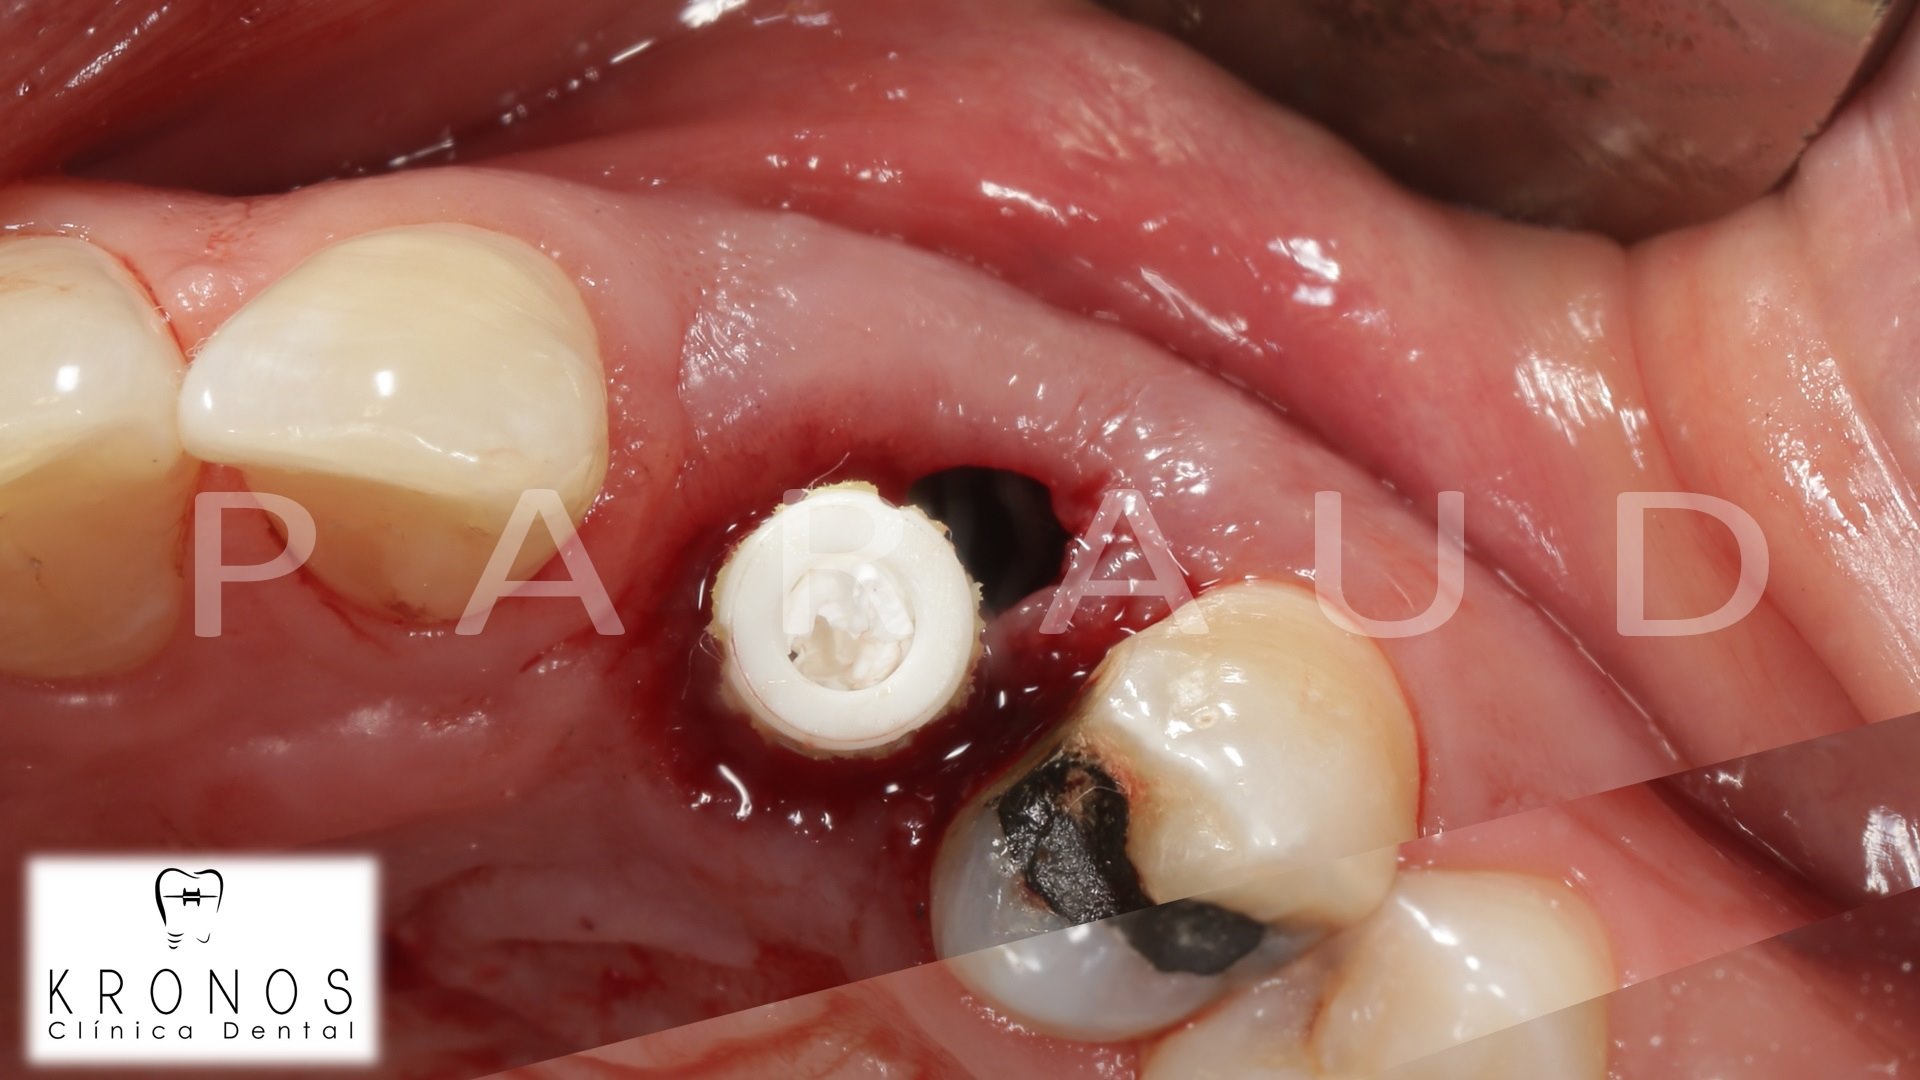

Clinical case: Digital Data Save concept in upper jaw premolar area

- Courtesy of Dr. Lysov Alexander Dmitrievich & Dr. Sofronov Matvey Vitalievich, Russia -

AnyRidge, R2GATE, R2GATE guide, ISQ value, initial stability, immediate loading, KnifeThread, maxillary posterior, #14, Digital, Dr. Lysov Alexander Dmitrievich, Dr. Sofronov Matvey Vitalievich, zirconia abutment, CAD/CAM crown

AnyRidge implant system, R2GATE, Digital prosthesis

“AnyRidge & R2GATE show stable results

after immediate extraction, immediate implant placement, & immediate loading,

even with low bone density.”